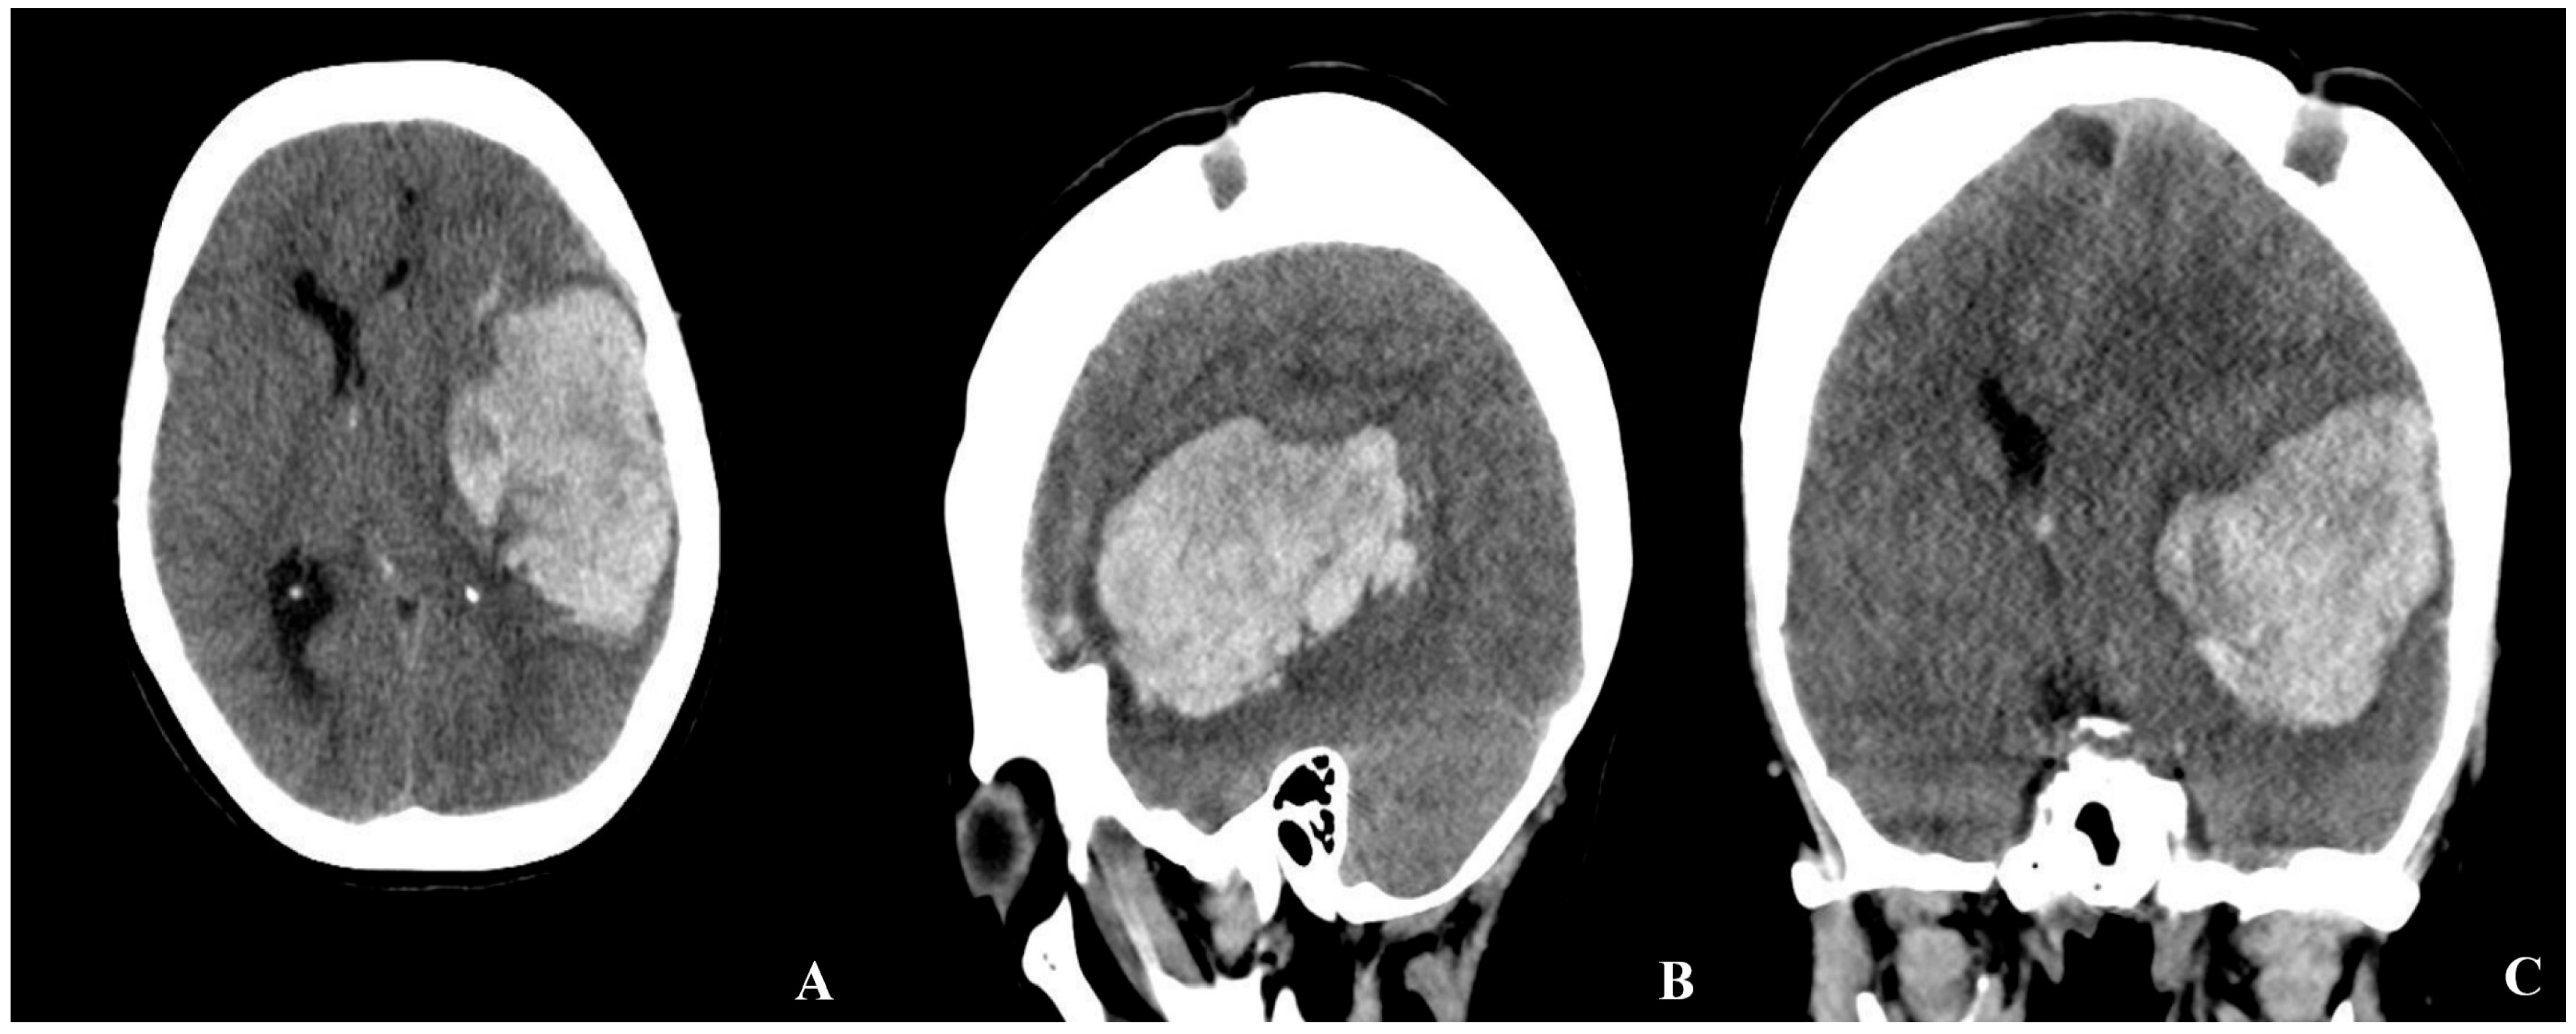

CT angiography revealed reduced calibers of the bilateral internal carotid arteries, along with prominent revascularization at the hematoma base and contralateral hemisphere. No aneurysms were identified (Figure 2).

Figure 2. Preoperative brain CTA of the patient ((A) axial, (B) coronal, white arrow: revascularized region adjacent to the hemorrhage).